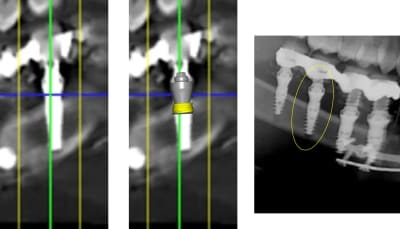

1 se baser sur la pano pour en tirer des conclusions est une erreur de débutant

2 sur les coupes scanner une partie du col est infra osseuse et l'autre non

> 1 se baser sur la pano pour en tirer des conclusions est une erreur de débutant

>

> 2 sur les coupes scanner une partie du col est infra osseuse et l'autre non

mais posit... y'a que toi qui pense que l'implant est aussi enfoui... ca saute aux yeux que tu fais tout pour grater 1mm d'enfouissement... pour qu'ils paraissent pas si mal posé que ca...

avec, par exemple, ton implant de 10mm qui est contenu dans 9mm... t'es le Gérard Majax des guides chir.

comme ici... si e carré fait 4,5 alors l’implant ne fait pas 10 mais moins de 9...

Tout comme l’autre implant pas 11,5 mais 10,3

heureusement que ta méthode est "précise" ;)

En traçant le col de l'implant comme tu le fais tu ne tiens pas compte que le pilier fait 4,5 mm de hauteur, normalement tu devrais arriver à le comprendre tout seul !